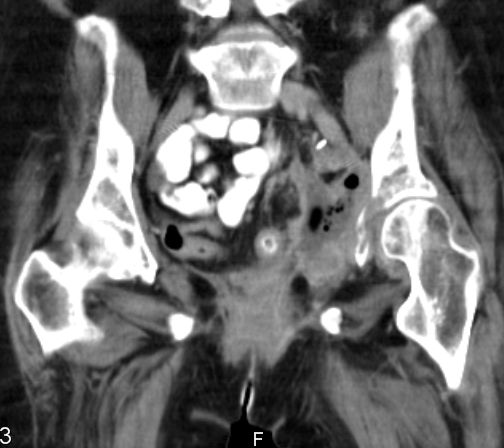

| Blase | 80-jähriger Mann mit ausgedehntem Blasentumor. Der Tumor

infiltriert auch das anliegende Fettgewebe und den Musculus rectus rechts .![]() |